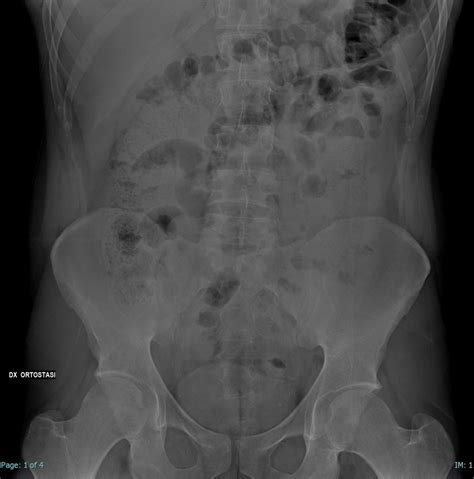

Diverticulitis symptoms commonly include abdominal pain, often localized to the lower left side. Other symptoms can include fever, chills, nausea, vomiting, and constipation or diarrhea. A proper diagnosis requires a medical evaluation.

This typically involves a physical exam, medical history review, and possibly imaging tests such as a CT scan. Accurate diagnosis is paramount for effective treatment.